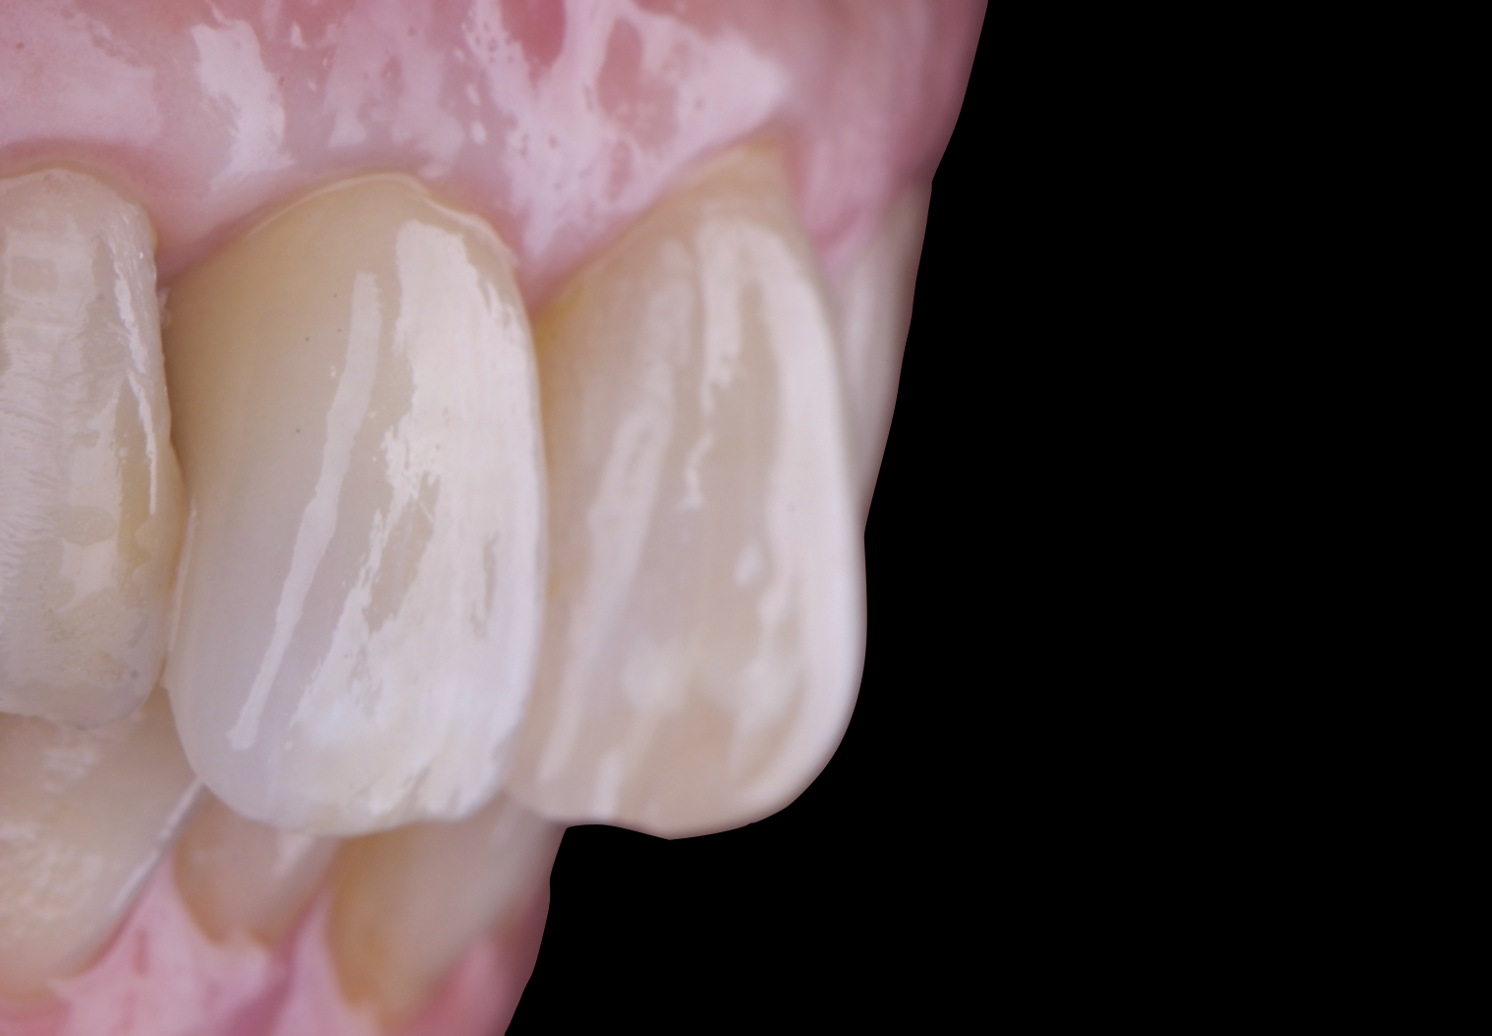

After an appropriate healing period, the definitive prosthesis was planned and delivered. A screw-retained zirconia crown was fabricated to ensure long-term durability, optimal esthetics, and retrievability. Zirconia was selected for its mechanical strength and excellent esthetic properties, blending seamlessly with the adjacent natural dentition in both form and color.

The final crown was designed to maintain the gingival architecture that had been shaped by the provisional. Special attention was paid to the emergence profile, contact points, and translucency to achieve harmony with the patient’s smile. The definitive restoration provided functional stability and esthetic integration, fulfilling the patient’s expectations for a fixed and natural solution.